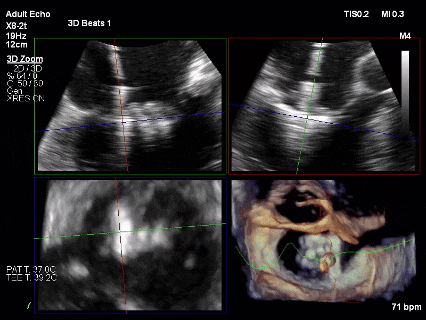

为了避免长时间TEE对食道造成损伤,术前即刻3D-TEE短时进一步明确二尖瓣病变相关解剖情况。

术前3D

3D-TEE二尖瓣相关解剖学参数:后叶长度:22-25mm,前叶长度:31-34mm;瓣环AP径:47mm,ML径:48mm;瓣口面积:约7.8cm²;脱垂宽度:30mm,最大连枷间距:14mm。

术前即刻TEE进一步明确了二尖瓣反流的机制(DMR)及反流程度(5+),重点完善了病变区域二尖瓣解剖结构的评估,预估手术难点/影响手术效果的解剖结构为冗长的二尖瓣后叶(PML约25mm),宽大的脱垂(Flail Width约30mm),超大的连枷间距(Flail gap约14mm)。

3D-Zoom下观察组织桥稳定,内侧残余脱垂

最终结果3D-Zoom-color显示组织桥稳定,原脱垂区域前后叶对合部分的脱垂已消除,反流降至1+以下